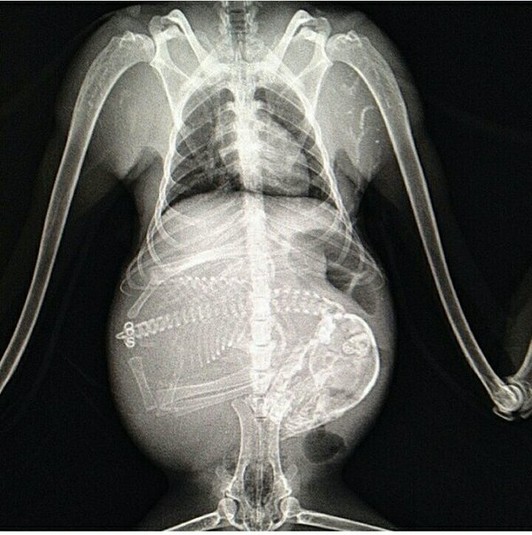

15 удивительных рентгеновских снимков беременных животных

Для женщины первое УЗИ запоминается на всю жизнь, но и рентгеновские снимки животных не менее удивительны

Мы все прекрасно представляем, как проходит беременность человека, и благодаря современным технологиям можем увидеть ребёнка в утробе матери на самых ранних стадиях, с разных ракурсов и даже в трёхмерной проекции.

Но а как же выглядит беременность у братьев наших меньших?

Специалисты, которые по долгу своей работы наблюдают животных, готовых принести потомство, поделились этими удивительными рентгеновскими и ультразвуковыми снимками.